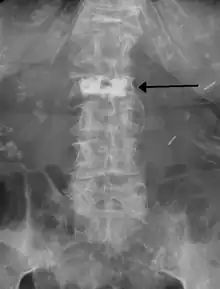

During the procedure, bone cement is injected with a biopsy needle into the collapsed or fractured vertebra. The needle is placed with fluoroscopic x-ray guidance. The cement (most commonly poly methyl methacrylate (PMMA), although more modern cements are used as well) quickly hardens and forms a support structure within the vertebra that provide stabilization and strength. The needle makes a small puncture in the patient's skin that is easily covered with a small bandage after the procedure.[2]